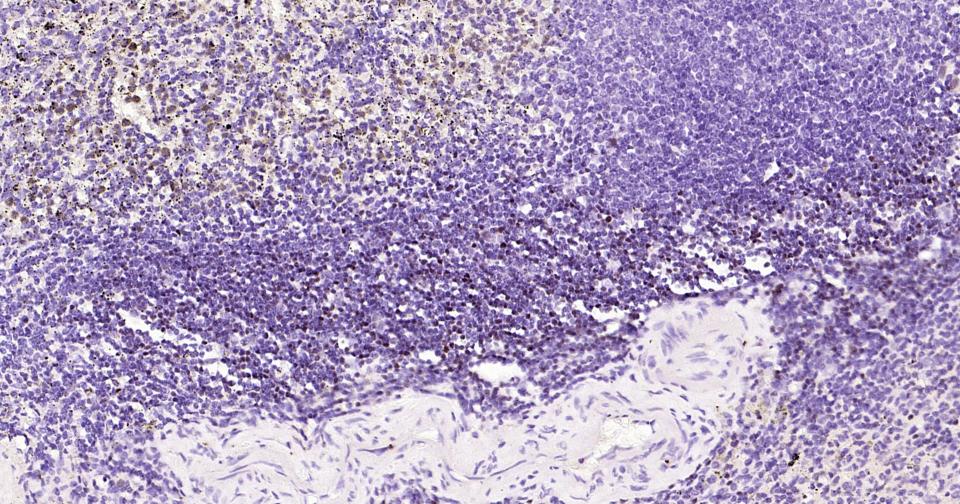

Paraformaldehyde-fixed, paraffin embedded Human Spleen; Antigen retrieval by boiling in sodium citrate buffer (pH6.0) for 15 min; Antibody incubation with LEF1 Monoclonal Antibody, Unconjugated(bsm-61170R) at 1:200 overnight at 4°C, followed by conjugation to the SP Kit (Rabbit, SP-0023)and DAB (C-0010) staining.